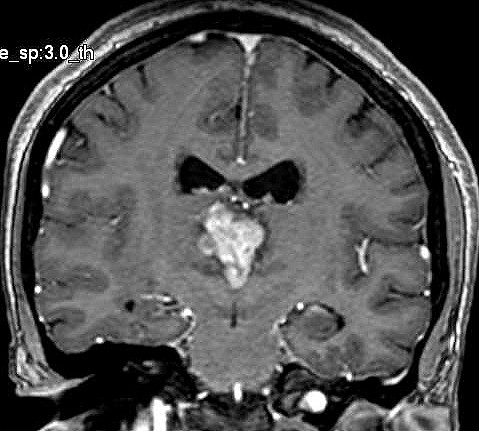

| Fem. 17a. |

| Nódulo sólido homogêneo preenchendo o III ventrículo, com limites precisos, com hipossinal em T1 e hipersinal em T2 e FLAIR, que se impregna por contraste paramagnético. Lesão menor implantada no assoalho do IV ventrículo provavelmente representa disseminação por via liquórica. |

| CORONAL, T2 | T1 COM CONTRASTE | |

| F. 17a. Tumor teratóide rabdóide atípico de III ventrículo. RM | HE | VIM, GFAP | HHF35, desmina, 1A4 | AE1AE3, EMA |